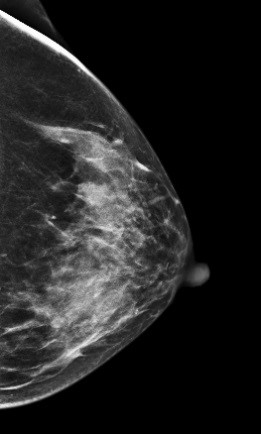

病例4 患者,36岁,常规检查,发现可疑,进一步检查。 2D图像:

影像描述: 常规2D图像MLO位左乳腺内见多个小结节影,下象限似见一团块影,边界模糊,CC位上并没有发现异常团块影,在V-Perview图像MLO位下象限见一类圆形团块影,部分边界尚清,但CC位上并没发现明显异常团块影,DBT断层图像在MLO和CC位上左乳内下象限清晰可见类圆形致密影,其边缘光滑锐利。 影像诊断: 左侧乳腺多发良性结节,BI-RADS 3。 病例点评: 最后病理证实纤维腺瘤,类似这样病例DBT可以给我们提供更多诊断信息有助于明确病变性质。